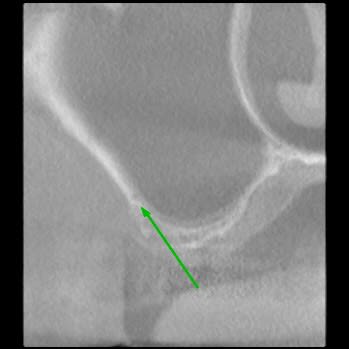

Je souhaite réaliser un sinus lift avec la pose de 2 implants en 15 et 16.

Mais sur le scanner je note la présence de l'artère alvéolo antrale intra osseuse, son trajet passe sur le site de mon futur volet.

1) ton artère est très basse, tu peux faire ton volet au dessus.

2) ton artère est toute petite et pas vraiment intra osseuse.

ici, comme signalé par CLIO, tu passes à l'aise par dessus.

Peu de risque pour l'artere alveolo-antrale.